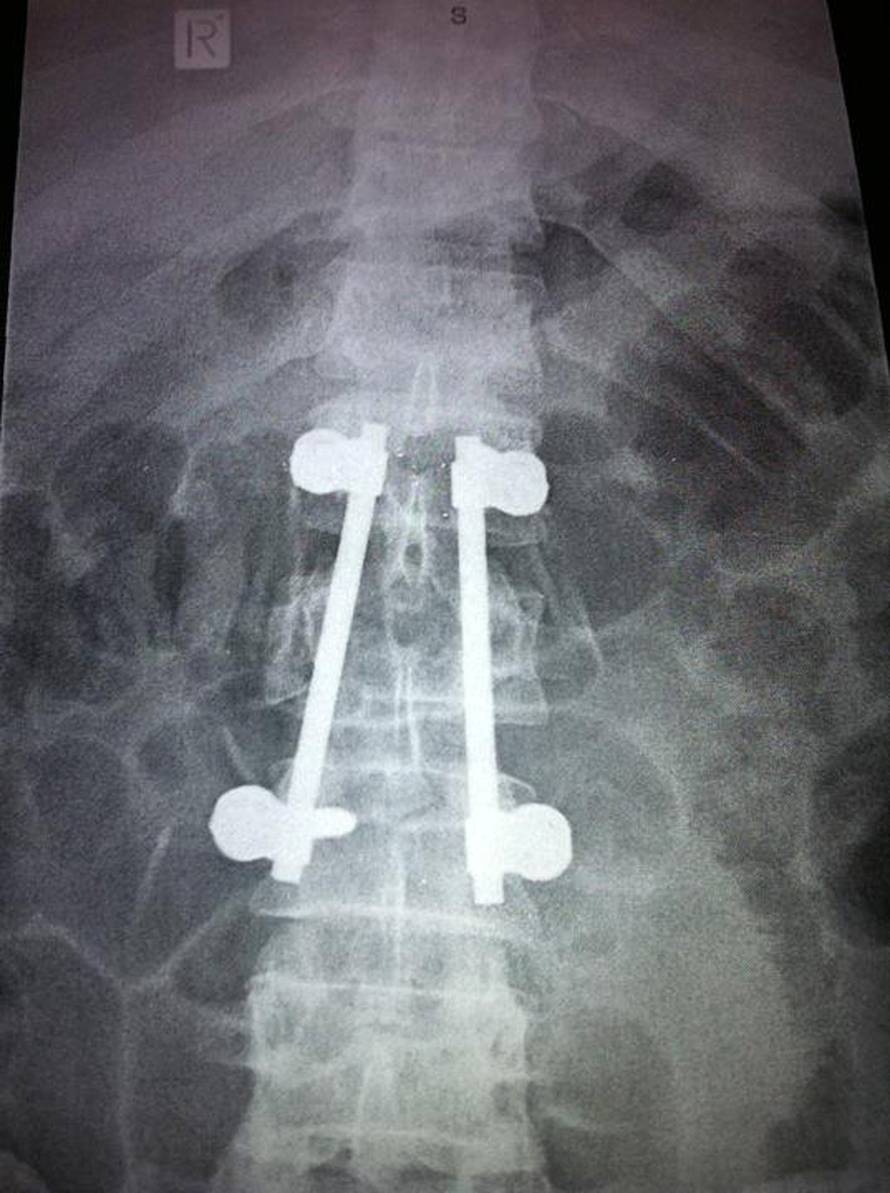

Liamu Dunneu (35) u skoku na Novom Zelandu zakazao je padobran, a rezervni je prekasno aktivirao. Pao je u kaljužu i slomio kralježnicu. Oporavlja se u bolnici